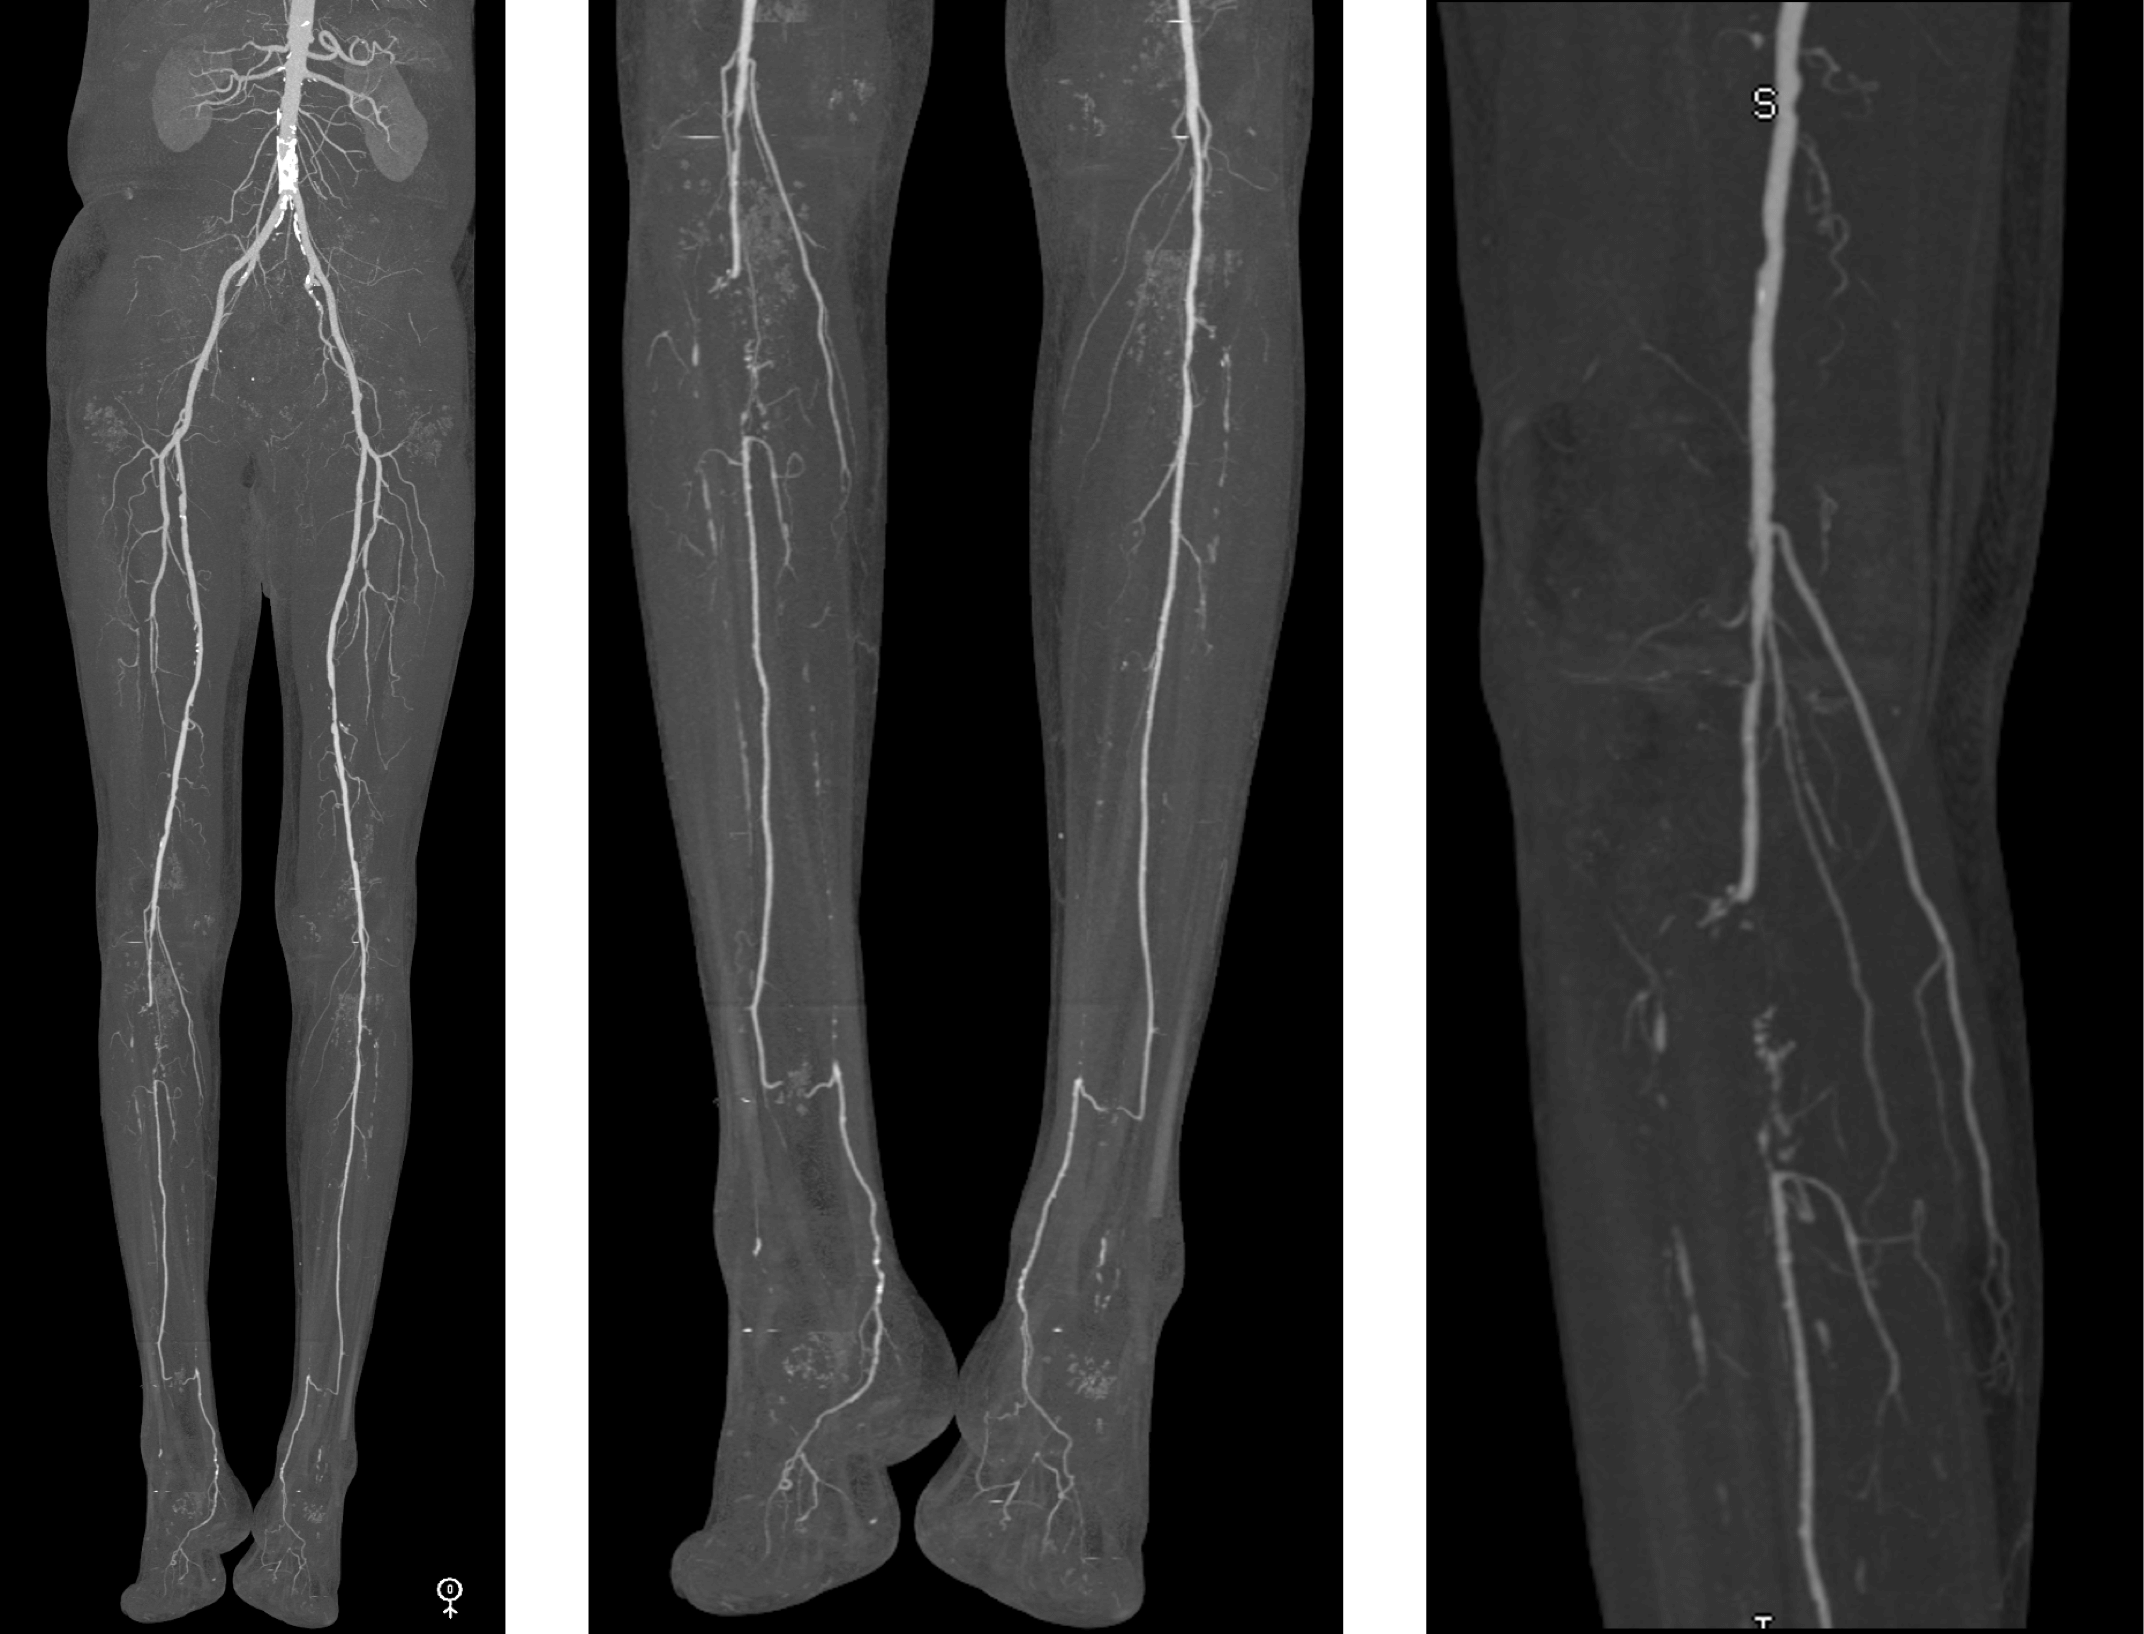

NEW: Bilateral, Symmetric Trifurcation Vessel Occlusive Disease with Additional Right Tibioperoneal Trunk Occlusion

67-year-old male smoker, presents with calf claudication (R > L)

Figure A-D: Right leg.

Figure A. Overview bone-segmented maximum intensity projection (MIP) image shows no significant inflow or femoropopliteal steno-occlusive disease.

Figure B. MIP image of right calf vessels shows occlusions of both the posterior tibial and anterior tibial arteries, with segmental occlusion of the proximal peroneal artery (arrow). There is peroneal reconstitution from adjacent collaterals including geniculate vessels (G).

Figure C. Small field of view MIP image shows collateral reconstitution of the peroneal artery. G = Geniculate artery branches.

Figure D. Small field of view MIP image at the ankle shows peroneal reconstitution of the posterior tibial artery (arrowheads), which continues patent across the ankle. Proximal to the reconstitution, calcifications within the occluded posterior tibial artery can be seen (* * *).

Figure E-G: Left leg.

Figure E. Overview bone-segmented maximum intensity projection (MIP) image shows no significant inflow or femoropopliteal steno-occlusive disease.

Figure F. MIP image of left calf shows occlusion of the posterior and anterior tibial arteries with patent peroneal artery to the distal calf (arrow).

Figure G. Small field of view MIP image shows peroneal reconstitution of the posterior tibial artery, which continues patent across the ankle into the foot. This anatomy is similar to the right side. The reason the patient was more symptomatic on the right is likely related to the absence of the proximal peroneal occlusion on the left side.